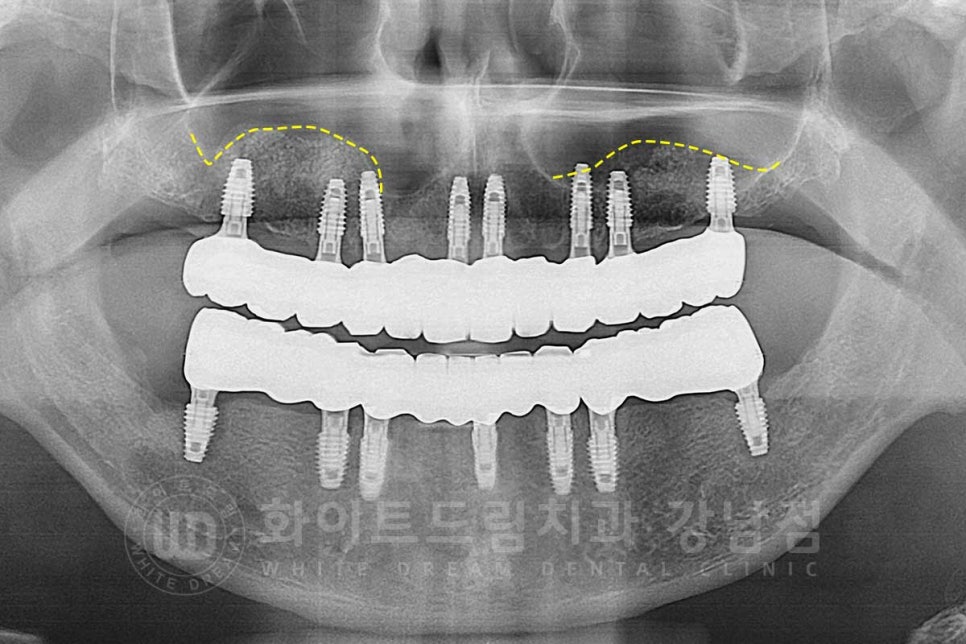

환자분의 상악 수술 후 x-ray 사진입니다.

23.08.12일 날 상악동 거상술을 동반한 14,13,11,21,23,24,26번 임플란트 식립까지

진행한 상태입니다.

치료 후 x-ray 사진입니다.

상악동 막도 잘 올라가고 이식된 뼈들도 새로운 뼈로 잘 만들어진 것이 확인됩니다.